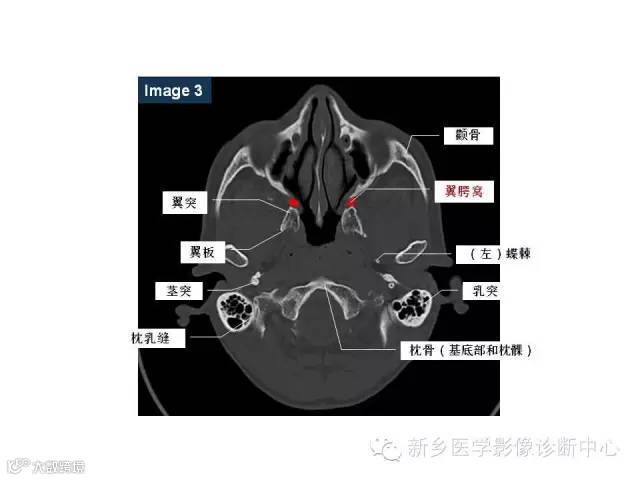

颅底孔道解剖详解

值得收藏!